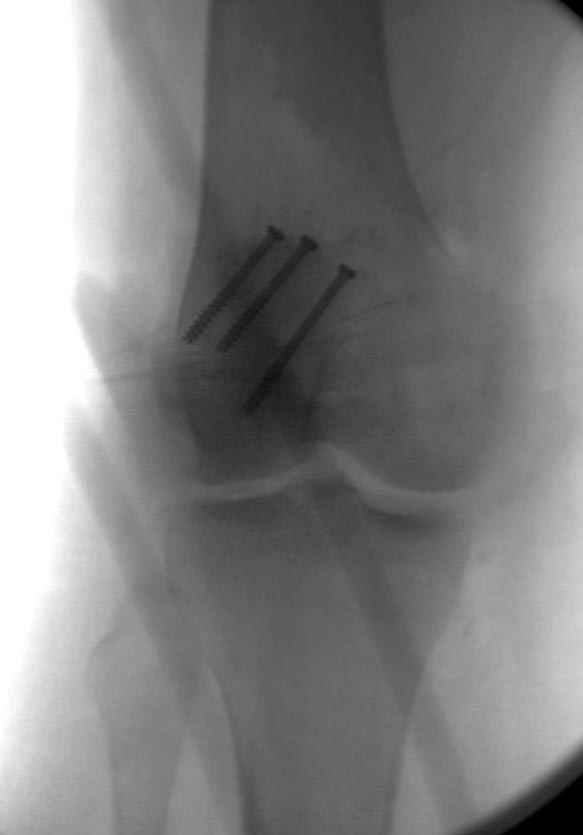

Внешний фиксатор держим около 6 недель, поэтому был выбран метод фиксации шурупами и еще линия перелома была диагональной, не было нужды в tension band technique, cannulated screws удобнее, провел спицы и по ним шурупы.

Связка ушита обычными сухожильными швами конец в конец, не было нужды проведения шва через надколенник, из-за ех-фиксатора.